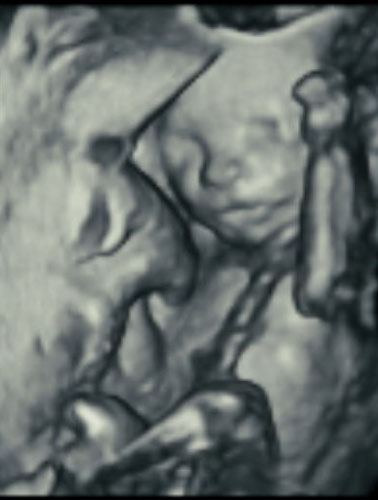

Here’s how ultrasound works in pregnancy: As early as 16 weeks, women can see a “fetal portrait” of their baby and determine its gender. Ultrasound technology has improved dramatically over the decades from flat, grainy black and white images to the current three-dimensional time experience.

Most hospitals offer some 3D scanning, but 3D ultrasound produces images that show the width, height and depth of a developing child. Rather than sending sound waves straight into the womb and recording when they bounce back as is common in 2D imaging, 3D ultrasound sends sound waves from different angles. A computer then renders a 3D image based on this data.

4D ultrasound adds movement as it occurs. The fourth dimension is time. You’re actually watching your baby live in 3D mode. How cool is that?